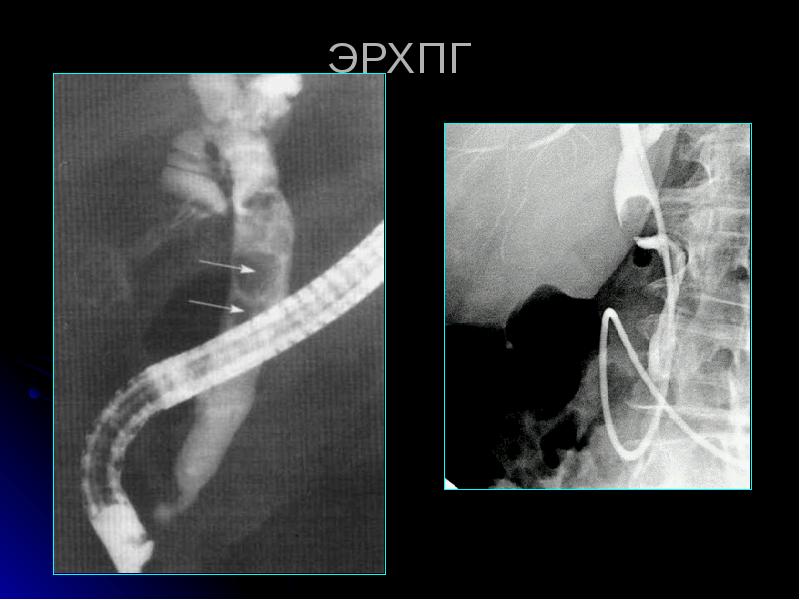

После эрхпг

После эрхпг 111 фотографий